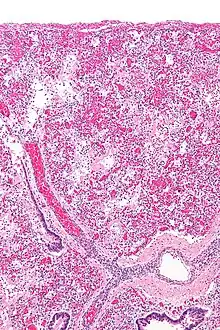

Micrograph of diffuse alveolar damage, the histologic correlate of ARDS. H&E stain.

ARDS is a form of fluid accumulation in the lungs not explained by heart failure (noncardiogenic pulmonary edema). It is typically provoked by an acute injury to the lungs that results in flooding of the lungs' microscopic air sacs responsible for the exchange of gases such as oxygen and carbon dioxide with capillaries in the lungs.[12] Additional common findings in ARDS include partial collapse of the lungs (atelectasis) and low levels of oxygen in the blood (hypoxemia). The clinical syndrome is associated with pathological findings including pneumonia, eosinophilic pneumonia, cryptogenic organizing pneumonia, acute fibrinous organizing pneumonia, and diffuse alveolar damage (DAD). Of these, the pathology most commonly associated with ARDS is DAD, which is characterized by a diffuse inflammation of lung tissue. The triggering insult to the tissue usually results in an initial release of chemical signals and other inflammatory mediators secreted by local epithelial and endothelial cells.

Neutrophils and some T-lymphocytes quickly migrate into the inflamed lung tissue and contribute in the amplification of the phenomenon. Typical histological presentation involves diffuse alveolar damage and hyaline membrane formation in alveolar walls. Although the triggering mechanisms are not completely understood, recent research has examined the role of inflammation and mechanical stress.